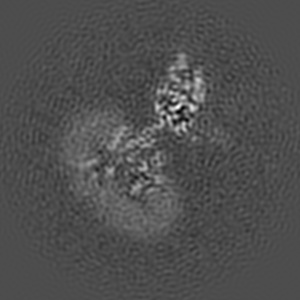

Cryo-EM structure of human GABA(B) receptor bound to the positive allosteric modulator rac-BHFF

Sample: Gamma-aminobutyric acid type B receptor

Structural Basis for Activation of the Heterodimeric GABA B Receptor.

Kim Y, Jeong E, Jeong JH, Kim Y, Cho Y

(2020) J Mol Biol , 432 , 5966 - 5984